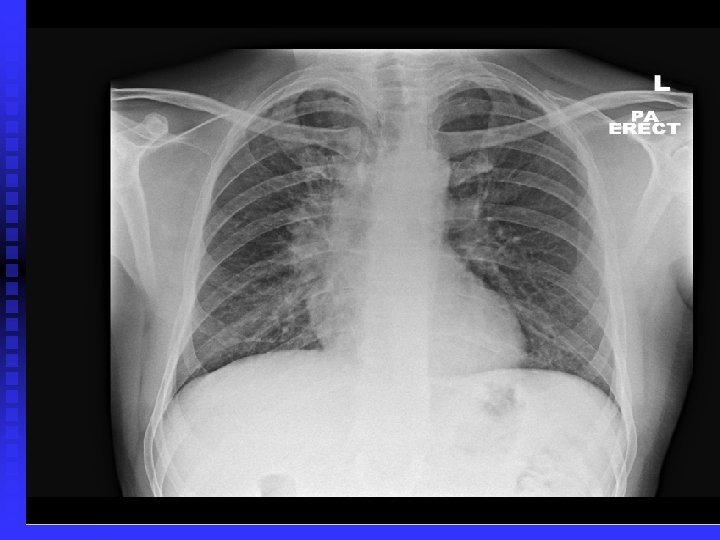

Case 1 50 year old Asian man n 30 pack year history of smoking n Strong family history of malignancy n Persistent cough for > 6 months n Frequent visits to GP: several course of antibiotics n Admitted to St. Helier Hospital with haemoptysis and weight loss n Cervical lymphadenopathy, clubbed n

Case 1 Tumour seen right upper lobe and right intermediate bronchus as Bronchoscopy n Poorly differentiated adenocarcinoma n Referred to RMH: Stage 4 disease, so palliative chemotherapy only n n Early chest X-ray and referral after onset of symptoms may have made a difference !